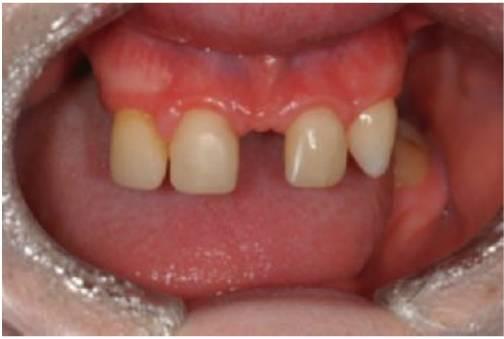

Los dientes son pequeños y cónicos y a menudo presentan un gran diastema anterior (fig. 9.3). Sus manifestaciones pueden limitarse a un solo diente ausente o a un incisivo lateral en clavija (v. hipótesis de Lyon, más adelante) y las mujeres heterocigóticas suelen ser diagnosticadas gracias a este tipo de dentición.

Tratamiento

El objetivo del tratamiento es proporcionar una función adecuada, mantener la dimensión vertical y restaurar el aspecto estético. La mejor opción desde el punto de vista de las consideraciones sociales es el inicio del tratamiento a los 2-3 años de edad. Sucede a menudo que los padres pretendan con ahínco «normalizar» el aspecto del niño. Un primer paso suele ser la colocación de restauraciones de composite para enmascarar el aspecto «similar a un colmillo» del diente anterior caniniforme (fig. 9.3A). Más adelante se efectuará la provisión de prótesis para que sufra menos burlas, sobre todo en el momento en que el niño empieza a ir a la escuela. La prótesis puede prepararse tan pronto como al niño se le puedan tomar impresiones, pero la realidad es que el primer juego de prótesis suele llevarse en el bolsillo y a medida que el niño crece se desarrolla el deseo de tener un aspecto más normal. Gracias a una incentivación y refuerzo positivo del niño, la mayoría de los niños llevarán puestas sus prótesis.